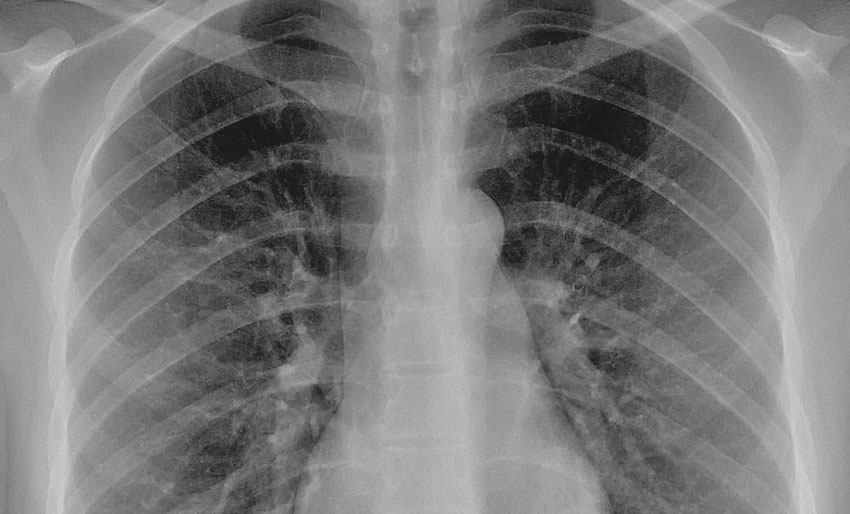

Et normalt røntgenbilde av lungene. Mikael Häggström/Wikipedia (public domain)